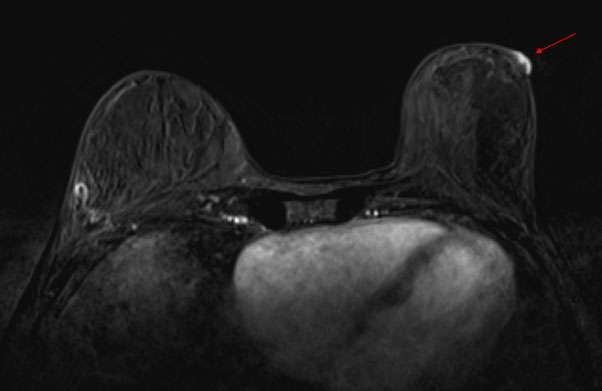

Case: Paget's Disease Figure 4

Figure 4: Contrast enhanced breast MRI of the same patient demonstrates linear non-mass enhancement in the upper outer quadrant of the left breast. MRI guided biopsy yielded an additional site of cancer.